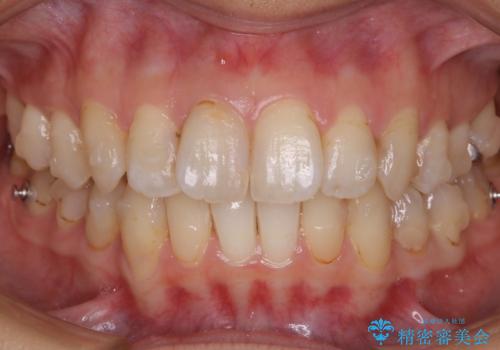

- 前歯のガタつきと噛み合わせの改善を希望してご来院されました。

目立たない装置での矯正治療をとのことでインビザラインを用いた非抜歯矯正を行うこととなりました。